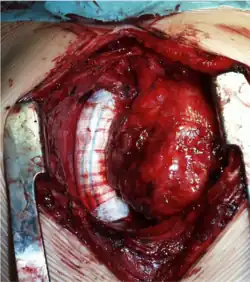

- zewnątrzsercową (obecnie preferowaną), gdzie żyłę dolną główną łączy się z prawą gałęzią płucną przy użyciu protezy wykonanej z Gore-Texu[2][12][13]. Po wprowadzeniu przez Marcellettiego w 1990 zewnątrzsercowego zespolenia VCI z tętnicą płucną metoda ta jest aktualnie metodą z wyboru (polecana jako najlepsza) i jest przeprowadzana najczęściej w krążeniu pozaustrojowym na bijącym sercu, ale może być też wykonana przy przeciwwskazaniach, bez użycia krążenia pozaustrojowego stosując na czas zespolenia omijające połączenie między VCI i prawym przedsionkiem serca[2][14].